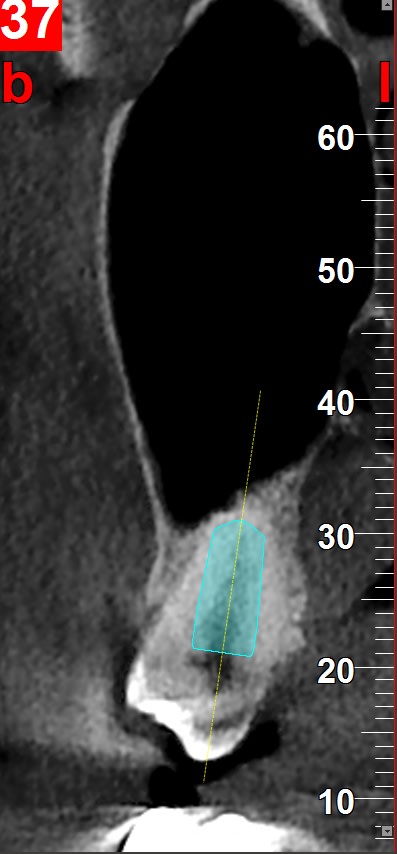

Par contre est ce que la mésialisation de la 18 est possible même si le sinus plonge au niveau de l'édentement de la 17 ancien et qu'il n'y a pas d'os en mésial ? Ça va se remanier tout seul ?

L'ortho sur 18, nonobstant le coût, j'aimerais bien voir comment la sagesse avance en étant déjà contre la corticale de la procidence sinusienne.

Juste pour info il n'y a pas de contre indication particulière à bouger une dent qui est contre le sinus. Dans certain cas ça peut ralentir le mouvement mais c'est plus ou moins tout. Clairement pas un soucie si il y a un implant.

Extraction de 16 et 26, 17 et 27 étant clairement contre le sinus.

aux autres, je dirai ceci: est-ce que dans votre pratique implantaire la corticale sinusienne est un obstacle impénétrable??? je connais la réponse puisque je suis aussi poseur d'implant comme vous....et bien évidement la réponse est non....

et bien c'est la même chose en ODF on peut déplacer une dent en déformant la corticale sinusienne, çà n'est absolument pas un problème...

si vous faites l'exo de la 8, même pas sûr que vous ne soyez pas obligé de faire un sinuslift car l'os dans cette zone se résorbe en général +++ voir disparaît avec la dent si la tubérosité vient avec la dent...